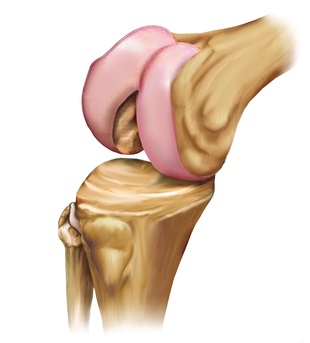

Warum brauche ich ein neues Kniegelenk?

Aus verschiedenen Gründen kann es im Knie zum Knorpelverschleiß (Arthrose) kommen, der die Gelenkflächen negativ verändert.

Gesundes Knie

Knie mit Arthrose